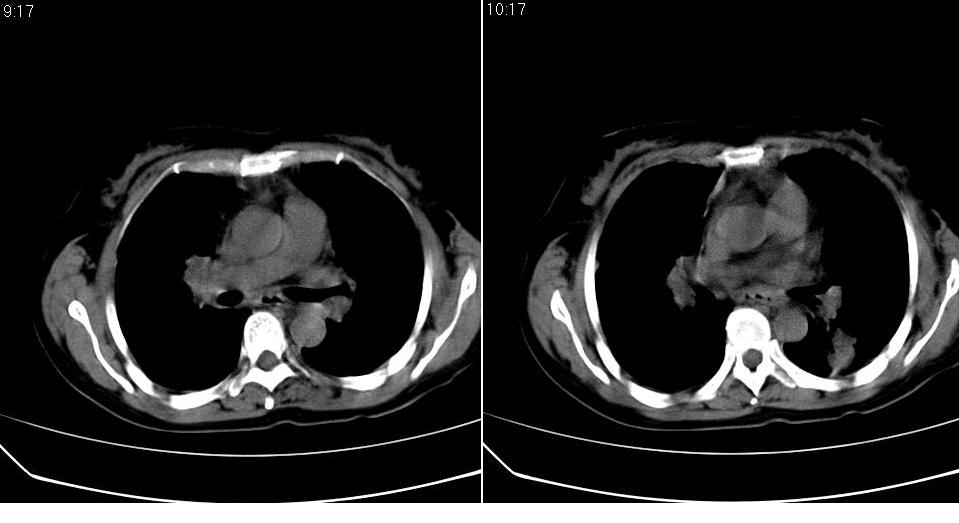

标题: CT16839:胸部CT平扫

女 50岁,在其他医院确诊肺癌.

支持 右肺上叶肺癌并两肺及纵隔转移。

考虑 肺癌伴肺及纵隔转移,心包膜增厚